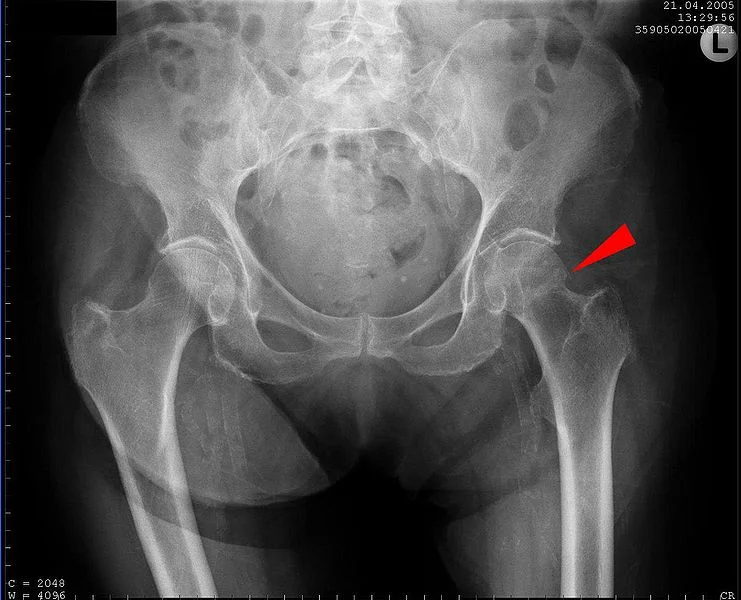

2. Pelvic Fracture: The Open Book You Don't Want to Read

Now being Family Medicine physicians in an urban setting, we tend not to see as much acute trauma. But since this fracture has the highest risk for mortality on the list, it's probably poor form to miss it. Now I'm not talking about the ol' regular, atraumatic, geriatric pelvic fracture here. Those don't tend to have as much hemorrhage risk to them. I'm talking about high force, high velocity fractures (MVA, skiing/snowboarding, twerking). In a couple different case series it was found that 38.5 and 34 percent of patient's with pelvic fractures required transfusions. [2,3]. Mortality rates for pelvic fractures can vary from the more common acetabular fractures (3%) to open pelvic fractures (45%) [4,5]

The name of the game here is proper diagnosis, which entails a good history of mechanism of injury as well as a good exam (ecchymosis in the surrounding area, pain on palpation, vaginal/rectal exam for open fracture, and compression of the pelvis). External compression isn't something I have a ton of experience with but this very serious and professional looking trauma doc has a nice blog entry on it. Basically, compress AP compression type fractures and not lateral or vertical fractures. Take a look at the video below on proper sheeting technique. Although, it's not completely accurate because a lot of your trauma patients will have their pants cut through so you wouldn't be able to tuck the sheet into them..